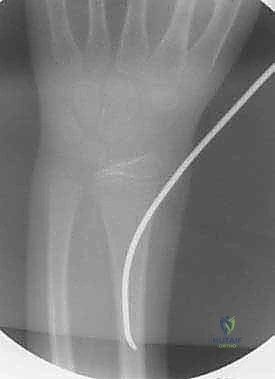

التشخيص الشعاعي الدقيق

في عيادة الأستاذ الدكتور محمد هطيف، لا يتم الاعتماد على الفحص السريري فقط. يُعد التشخيص الشعاعي الدقيق حجر الزاوية في تحديد خطة العلاج:

- الأشعة السينية (X-rays): يتم أخذ صور بأوضاع مختلفة (أمامي خلفي AP وجانبي Lateral). يصر الدكتور هطيف دائماً على أن تشمل الأشعة المفصل الذي يعلو الكسر (الكوع) والمفصل الذي يليه (الرسغ) لضمان عدم وجود كسور أو خلوع خفية (مثل كسور مونتيجيا أو جاليازي).

تُعد تقنية التثبيت بالمسامير المرنة داخل النخاع (Flexible Intramedullary Nailing - FIN) أو مسامير التيتانيوم المرنة (Titanium Elastic Nails - TENs) المعيار الذهبي (Gold Standard) لعلاج كسور الساعد غير المستقرة لدى الأطفال. والأستاذ الدكتور محمد هطيف هو رائد هذه التقنية في اليمن.

1. التخطيط قبل الجراحة واختيار المسامير

قبل بدء العملية، يقوم الدكتور هطيف بدراسة الأشعة السينية بعناية لتحديد قطر المسامير المناسب. القاعدة الذهبية هي أن يملأ المسماران معاً حوالي 80% من أضيق نقطة في التجويف النخاعي. يتم ثني المسامير مسبقاً لتحقيق أقصى قدر من الاستقرار.